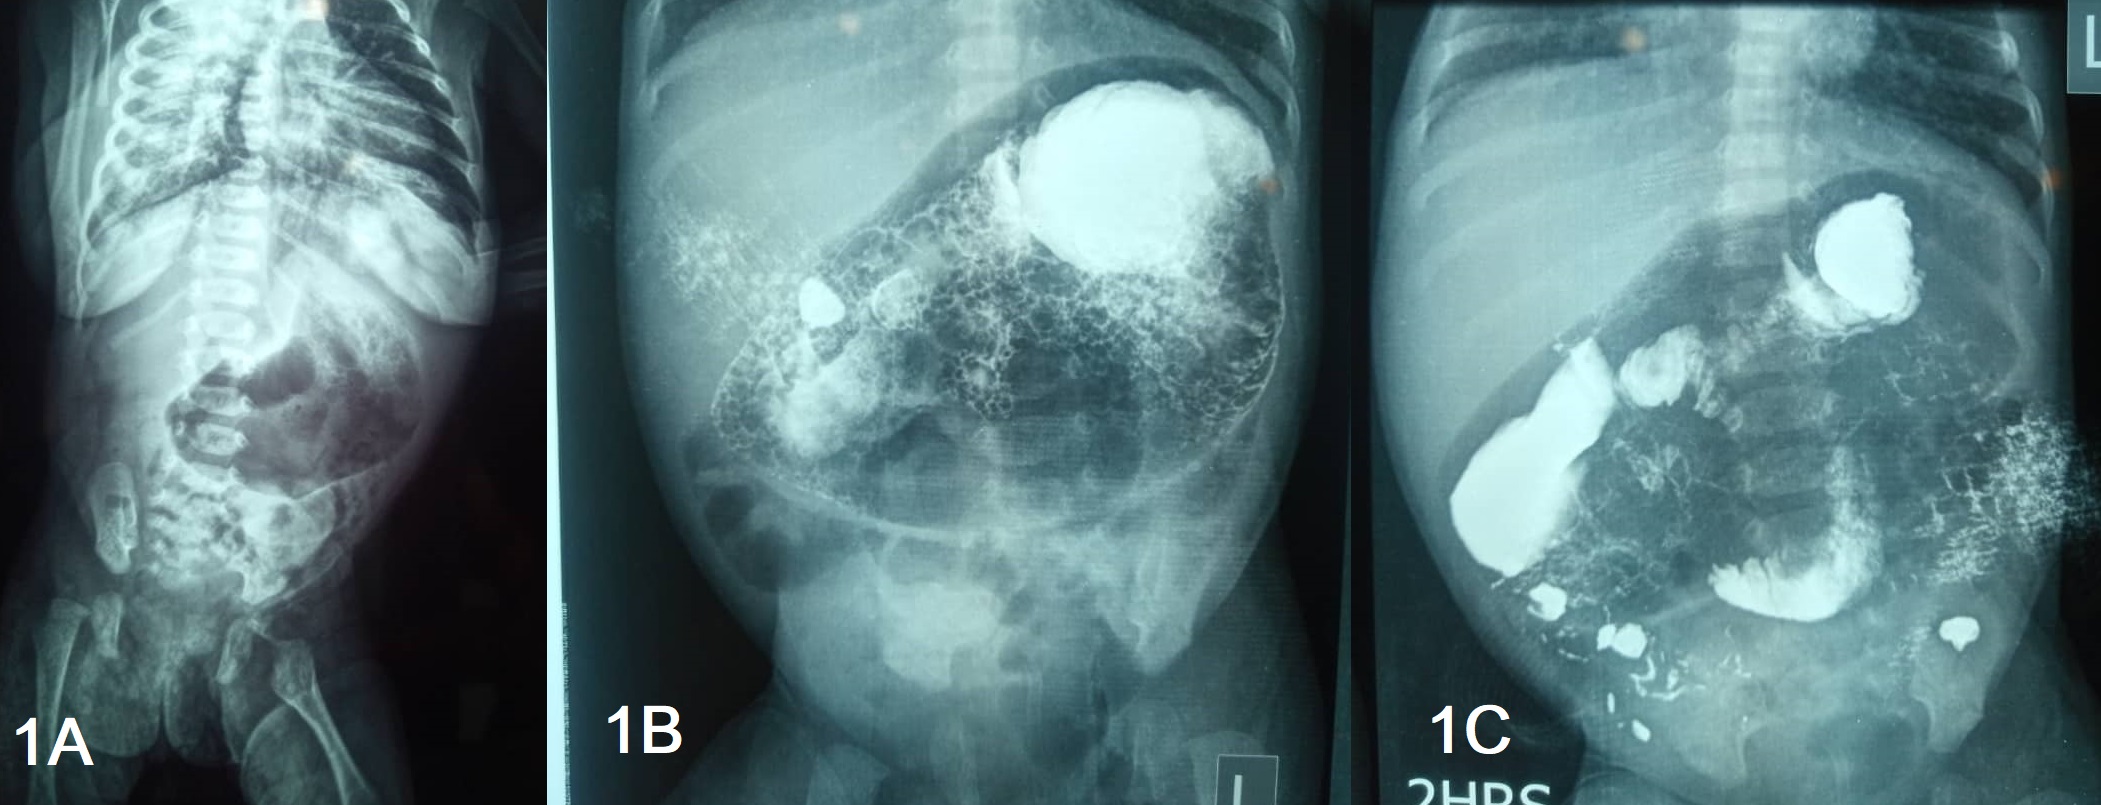

At exploratory laparotomy on the 19th day of life, the whole small bowel was enclosed in a thin membrane formed by the greater omentum, the neck of the sac was narrow entrapping the afferent and efferent loops of the small bowel which traversed it (Fig. 2A, 2B). The whole large bowel was located on the right, peritonealized, and enclosed in the same sac lying parallel to the small bowel which was lying anterolaterally on the left (Fig. 2C). The sigmoid colon runs straight down to the rectum in the midline without forming its loop. The stomach and duodenum were dilated and the duodenojejunal junction was in the normal position to the left of the vertebra, the caecum was below the liver towards the epigastrium. Other viscera were normal in appearance and position. The whole small bowel was extracted through the neck of the sac and there were no interloop adhesions, but bands were holding the mesentery together. The Sac, which was the omentum, was formed by the parallel lying ascending and descending colon with the transverse colon at the summit. The peritoneum over the large bowel was released to separate the colon which had narrow mesocolon and Ladd’s procedure was done for the small bowel which also had narrow mesentery. Appendectomy was then done to prevent future diagnostic dilemmas.

In this case, the cocoon was formed by the greater omentum, which has not been described before in English literature. It was a thin vascular membrane that folded on itself and formed a cord-like tissue at the neck of the sac, there were no adhesions found suggesting the absence of preceding inflammatory events.

Figure 2

A) small and large bowel wrapped in the omental sac. B) Narrow neck of the sac (arrow) through which the bowel was extracted. C) Relative position of the small and large bowel in the sac.